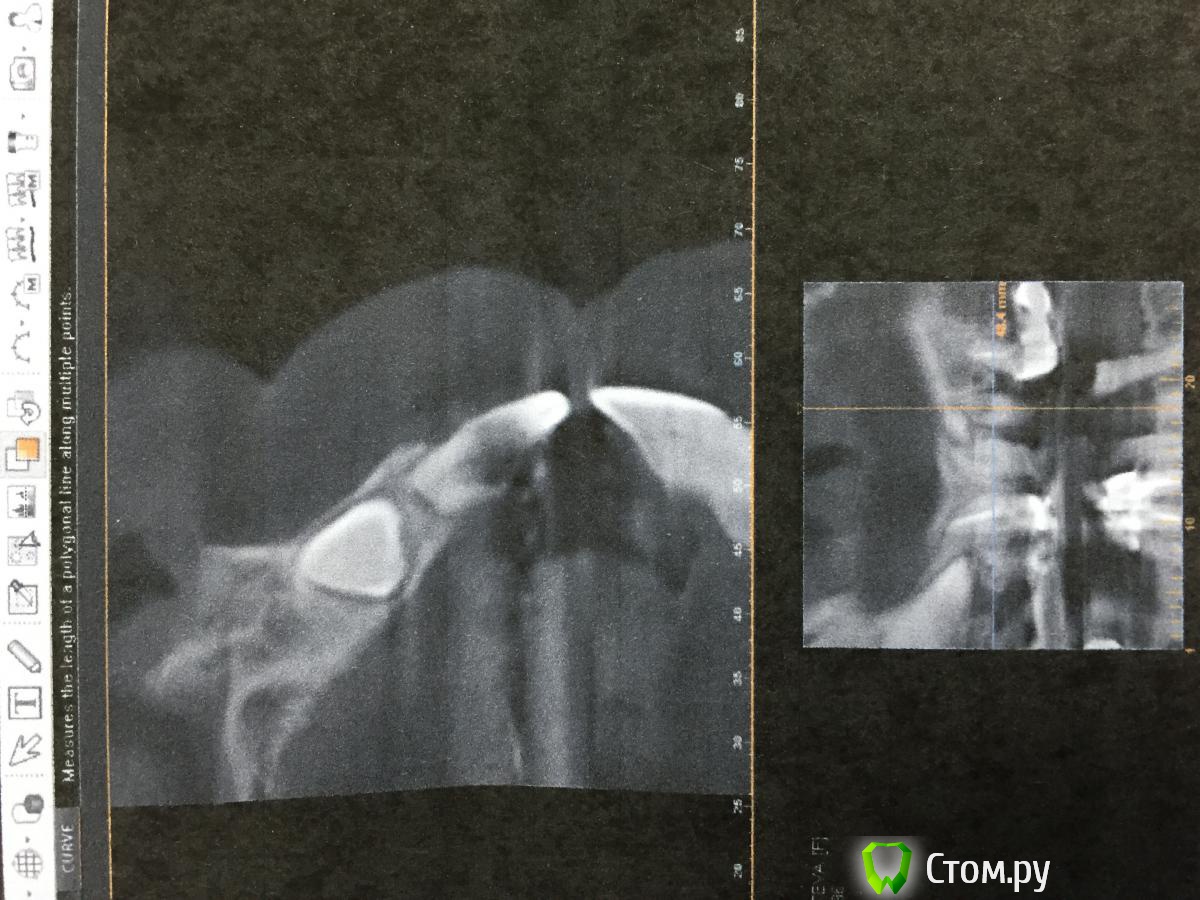

Opimar Опубликовано 18 ноября, 2014 Поделиться Опубликовано 18 ноября, 2014 Здравствуйте. Вот как мне кажется интересный случай. Пациентка 57 лет. На верхней челюсти одиночные 21,22. Мост на 11 и 12. Жалобы на подвижность и боли в области 11,12. На ОПТГ обнаружена ретенция, дистопия 13,23. Была направлена к терапевту для перелечивания 11,12,21 и 22. В процессе работы у терапевта возникли сомнения по поводу состоятельности корней зубов. Направлена на КТ. На КТ резорбция корней на 1/2 из-за клыков. Принято решение об удалении 11,12,21,22, ретенированных 13 и 23 с последующей костной пластикой и имплантацией через 6мес. Собственно сегодня выполнен первый этап: 1. Удалил 11,12,21,22 2. Трапецивидный лоскут от 11-22. 3. С помощью бор машины выпиливание 23 с разделением зуба на 2 фрагмента. 4.кюретаж лунки5.мобилизация лоскута6.заполнение лунки 23 Osteobiol mp3, сверху мембрана Evolution 7.фиксация лоскута Vicryl 4-0, Корален 4-0.Холод на область операции, антибиотикопрофилактику начали еще вчера.Удаление уложилось в 1.5 часа+ 30 мин подсадка и швы. Теперь вот думаю когда заниматься 13 и стоит ли? Может попытаться имплантанты мимо него поставить? Спасибо. Ссылка на комментарий